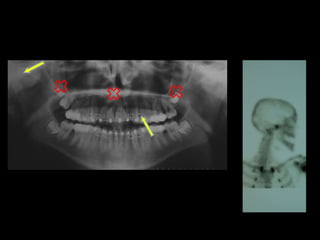

Hiperplasia condílea dcha

v v

Anquilosis ATM dcha